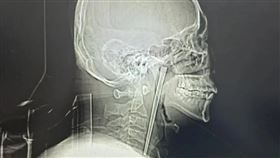

男誤吞12公分筷子 「卡喉嚨8年」才取出

中國遼寧省大連市一名46歲王姓男子,近日因為咽部突然...